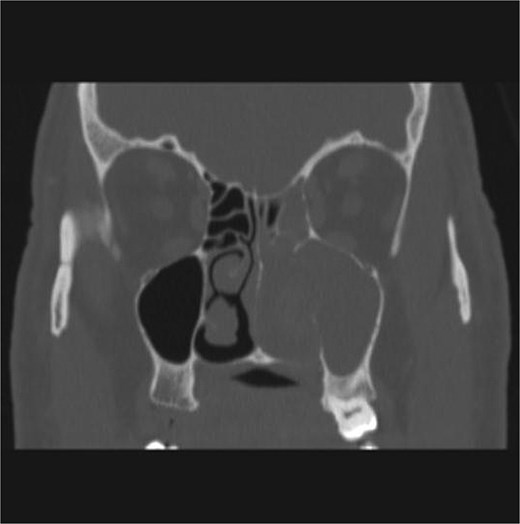

The patient underwent staging CT which was negative for distant metastasis. He then went underwent incomplete medial maxillectomy, ethmoidectomy, and sphenoidotomy followed by 10 sessions of immunotherapy abroad. He presented to our institution for follow up 6 months later with history of left nasal block and epistaxis. Nasal flexible scope showed a reddish nasal mass with greenish secretions (Fig. 3). Follow up CT revealed tumor recurrence (Figs 4 and 5). He was advised for multidisciplinary team evaluation to plan the treatment but he refused any intervention and lost follow up.

Coronal section of CT paranasal sinus soft tissue window showing the mass occupying the left nasal cavity and extending to maxillary and ethmoidal sinus, and reaching base of skull.